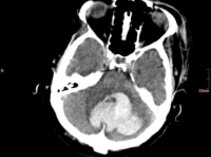

Intrazerebrale Blutung

Die intrazerebrale Blutung, also eine Blutung im Gehirn, tritt plötzlich auf und ist die schlimmste Form des Schlaganfalles.

Manchmal kann die Behandlung durch Evakuation mittels Operation oder Katheterpunktion mit Lysetherapie erfolgreich sein um die Stabilisierung des Patienten zu erreichen und um ein weiteres oder Nachbluten zu verhindern.

Wir bevorzugen – wenn notwendig und wenn möglich – die "bedside" Direktpunktion mittels Katheter und nachfolgende Lyse. Es ist eine minimal invasive, schnelle und effektive Behandlungsmethode.